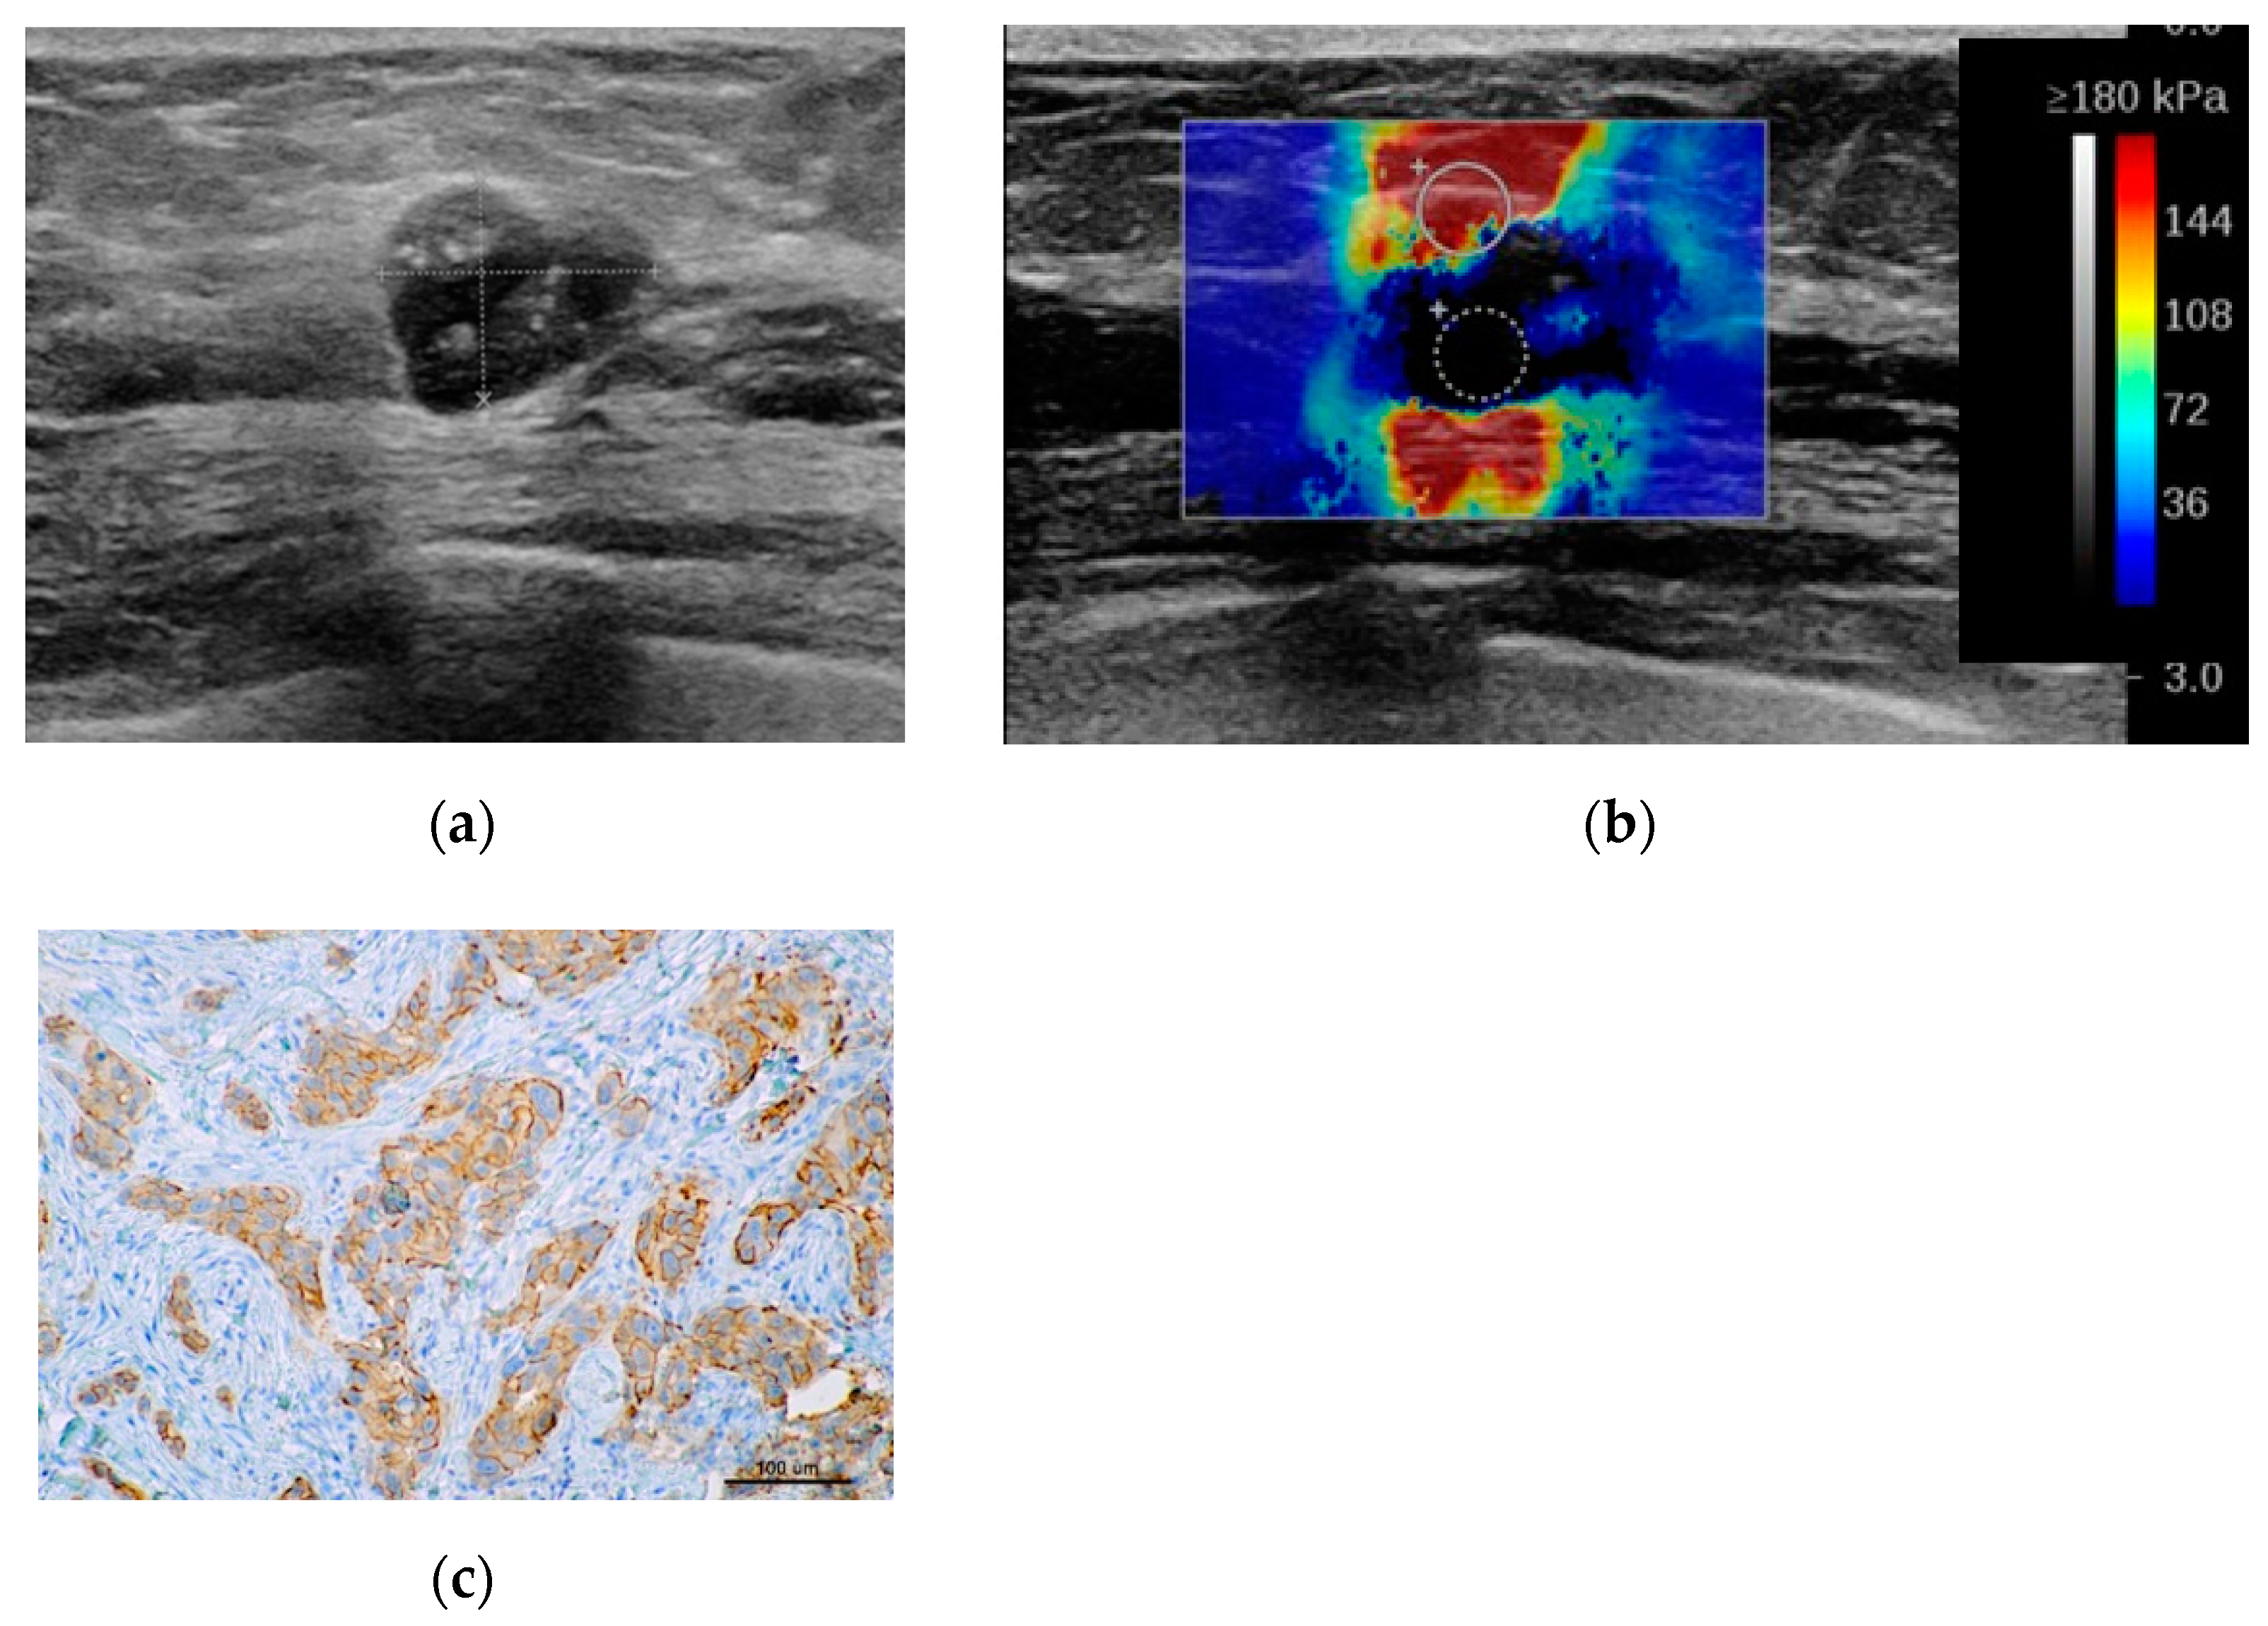

2.2. Sonoelastography